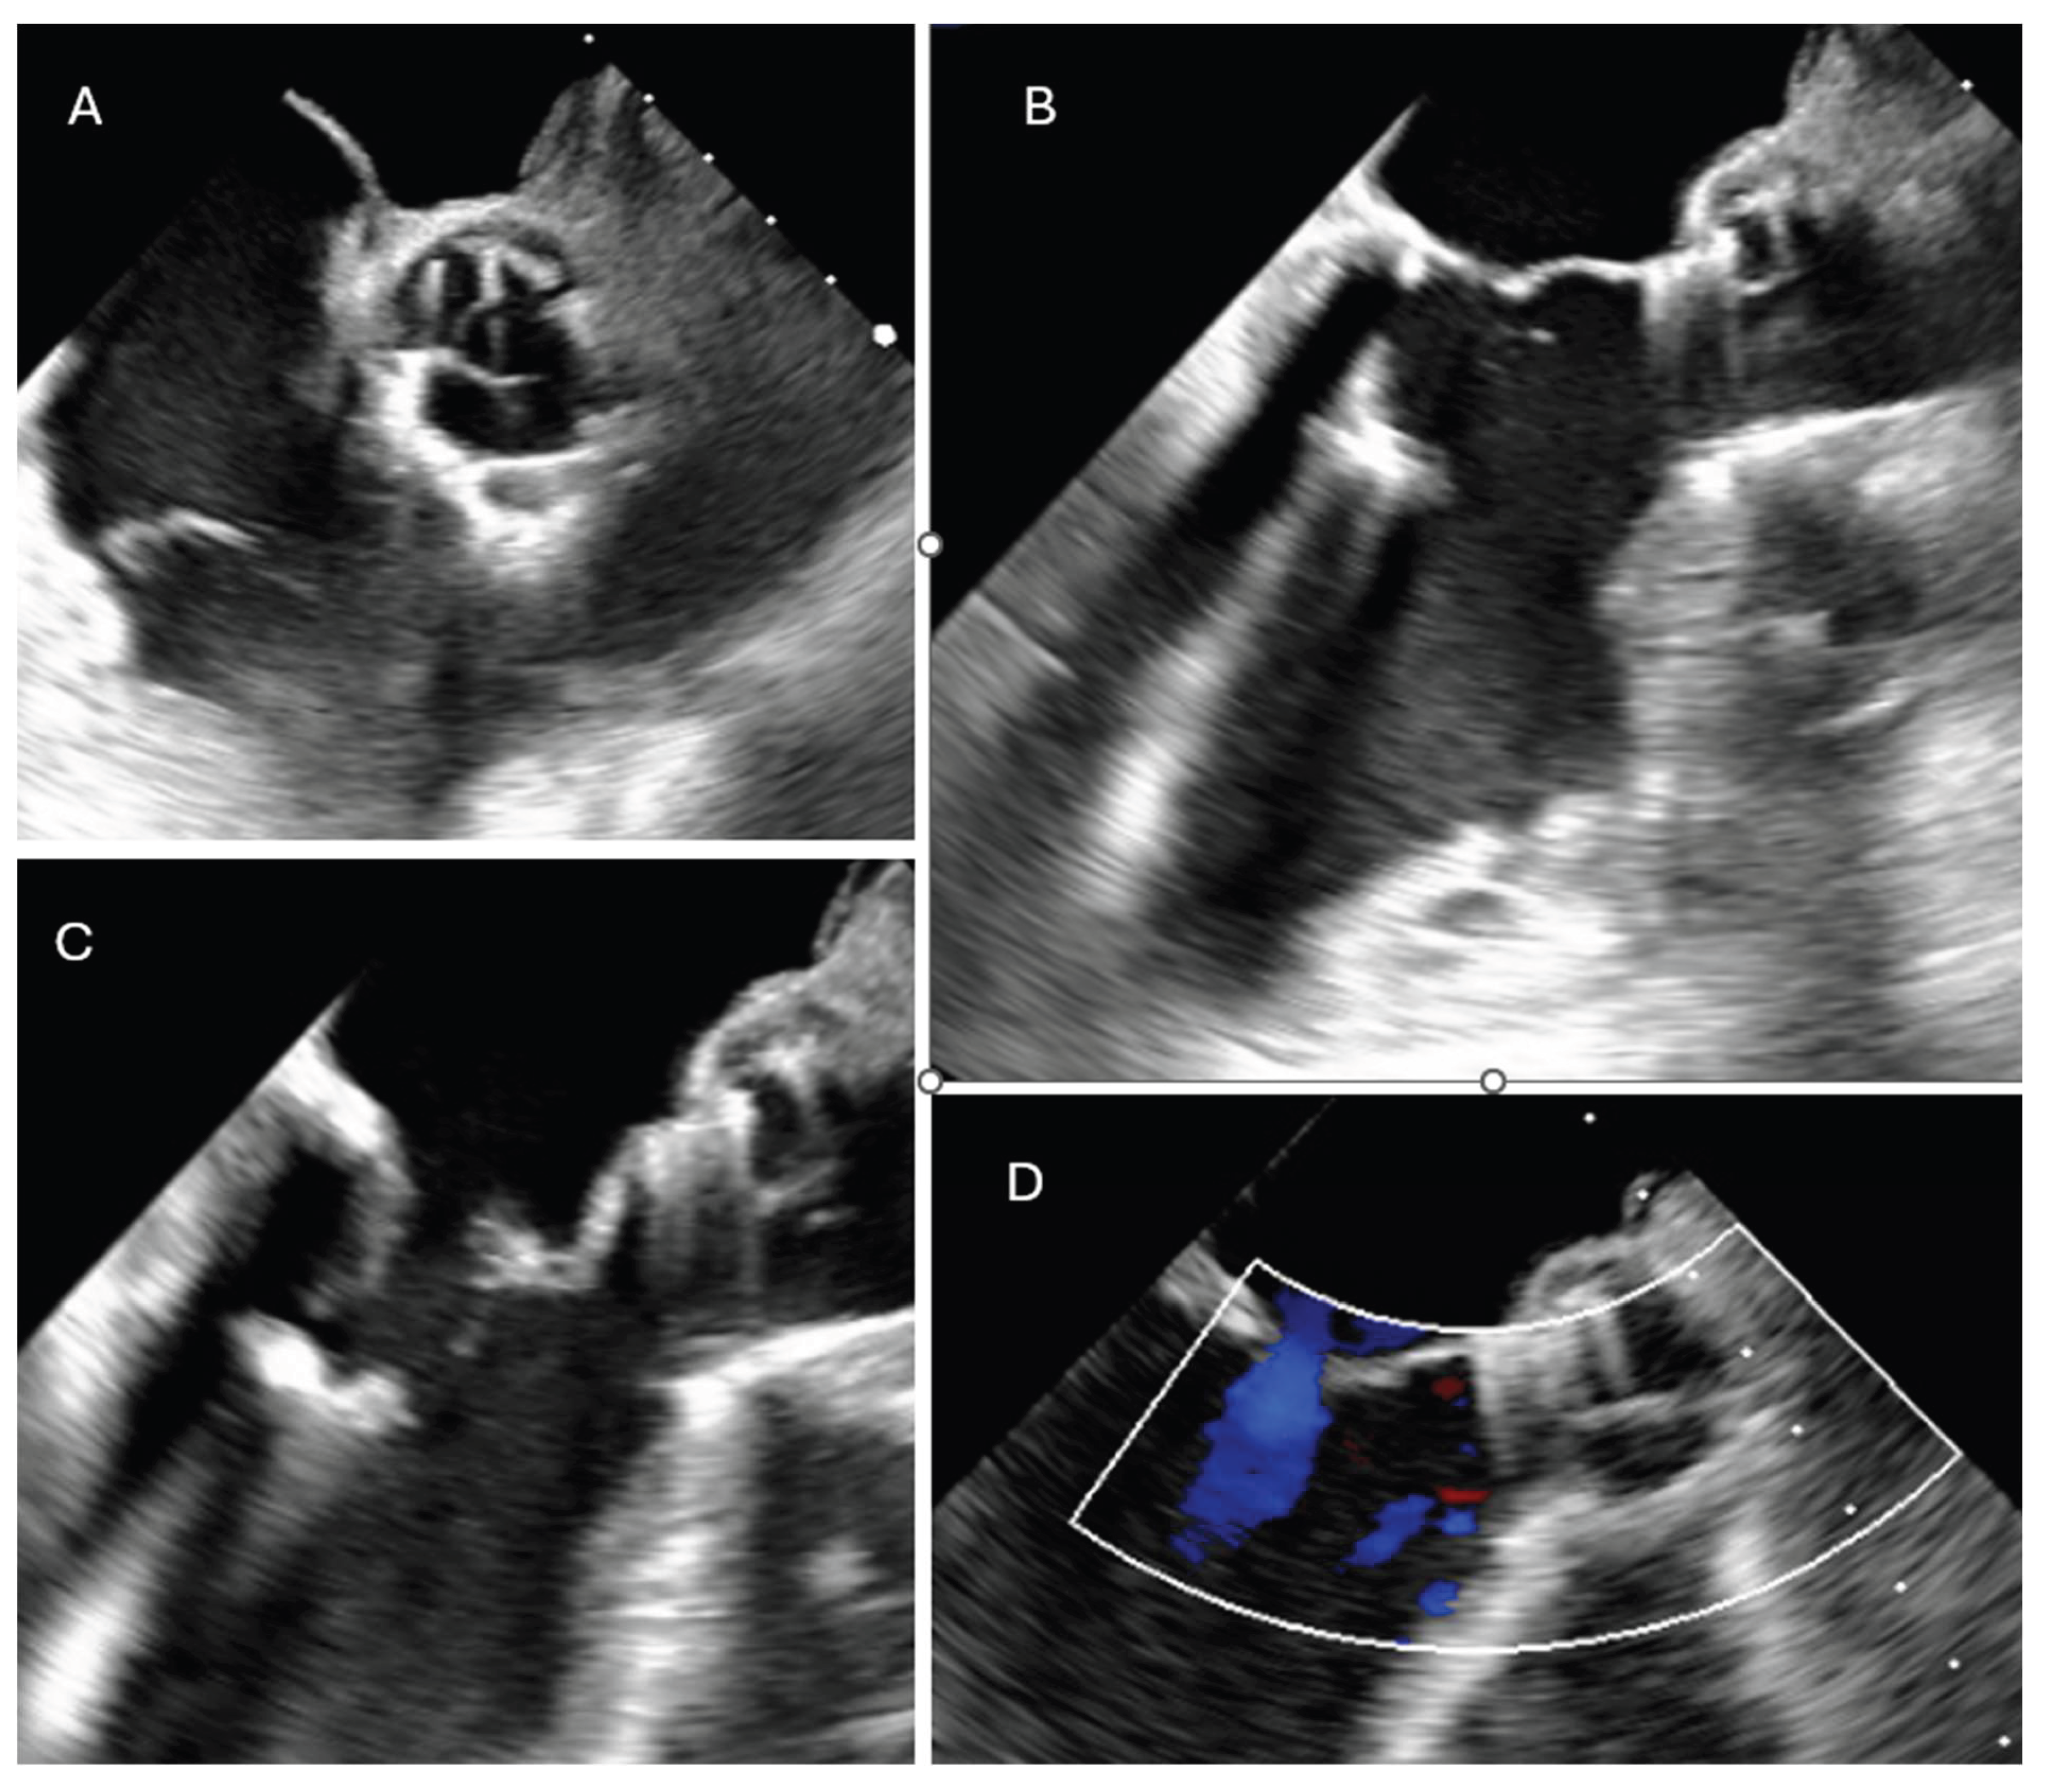

A 68-year-old male with a previous surgical history of Ozaki aortic valve reconstruction and LIMA-LAD coronary artery bypass grafting in 2023 for bicuspid aortic valve disease presented with acute decompensated heart failure. Blood cultures yielded Streptococcus bovis, and transesophageal echocardiography (TOE) revealed torrential aortic regurgitation due to destruction of the anterior neocuspidal leaflet, with associated large, mobile vegetations. (Figure 1)

Figure 1. Pre-operative trans-esophageal echocardiography revealed severe aortic regurgitation resulting from extensive destruction of the non-coronary cusp, accompanied by multiple mobile vegetations consistent with active infective endocarditis.